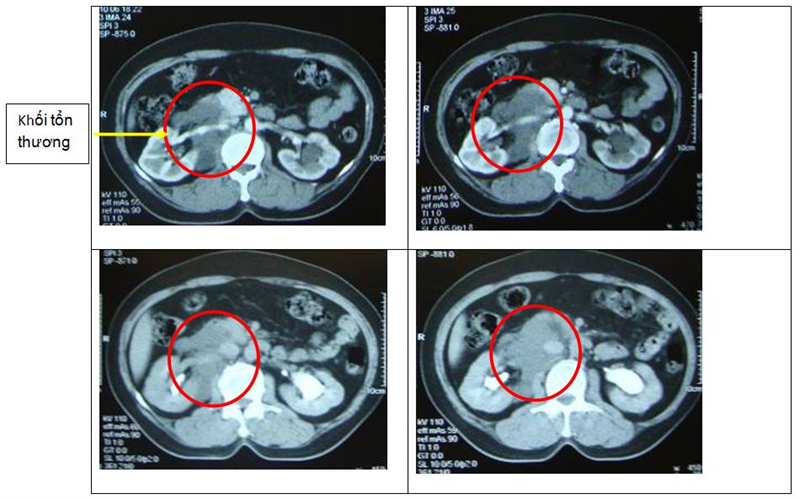

+ Ngày 23 tháng 9 năm 2011 tiến hành chụp CT ổ bụng: Tổn thương tỷ trọng tổ chức dạng hạch thâm nhiễm quanh tĩnh mạch chủ bụng từ ngang mức đoạn tách của tĩnh mạch thận đến trên chỗ chia của tĩnh mạch đùi, bờ không đều, ranh giới không rõ, kích thước khoảng  65x70mm, ngấm thuốc sau tiêm.

Kết luận: Hạch lớn quanh tĩnh mạch chủ dưới, giãn bể thận-niệu quản trái đoạn 1/3 trên

Bệnh nhân được chụp lại phim cắt lớp vi tính 64 dãy ổ bụng để đánh giá tình trạng bệnh cho thấy tổn thương u đã tan hết, không thấy hình ảnh khí và dịch trong nang, còn tồn tại vỏ nang. Không thấy rõ hình ảnh sỏi thận 2 bên, niệu quản 2 bên không giãn. Nang thận trái đường kính 1cm